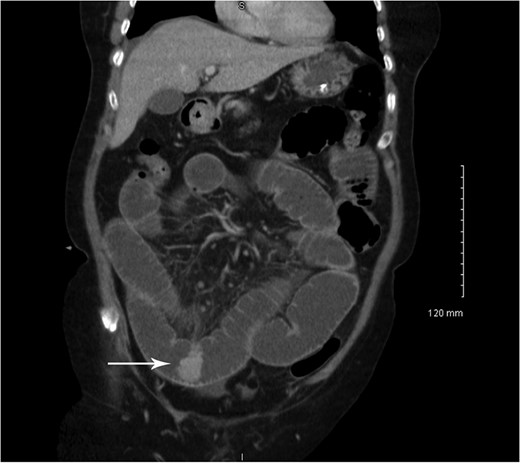

Coronal CT showing small bowel to small bowel intussusception (arrow).

Coronal CT showing small bowel mucosal-enhancing lesion (arrow).